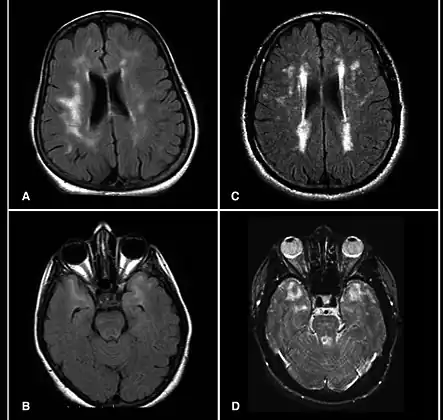

A hyperintensity or T2 hyperintensity is an area of high intensity on types of magnetic resonance imaging (MRI) scans of the brain of a human or of another mammal that reflect lesions produced largely by demyelination and axonal loss. These small regions of high intensity are observed on T2 weighted MRI images (typically created using 3D FLAIR) within cerebral white matter (white matter lesions, white matter hyperintensities or WMH)[1][2] or subcortical gray matter (gray matter hyperintensities or GMH). The volume and frequency is strongly associated with increasing age.[2] They are also seen in a number of neurological disorders and psychiatric illnesses. For example, deep white matter hyperintensities are 2.5 to 3 times more likely to occur in bipolar disorder and major depressive disorder than control subjects.[3][4] WMH volume, calculated as a potential diagnostic measure, has been shown to correlate to certain cognitive factors.[5] Hyperintensities appear as "bright signals" (bright areas) on an MRI image and the term "bright signal" is occasionally used as a synonym for a hyperintensity.

Hyperintensities are commonly divided into 3 types depending on the region of the brain where they are found. Deep white matter hyperintensities occur deep within white matter, periventricular white matter hyperintensities occur adjacent to the lateral ventricles and subcortical hyperintensities occur in the basal ganglia.